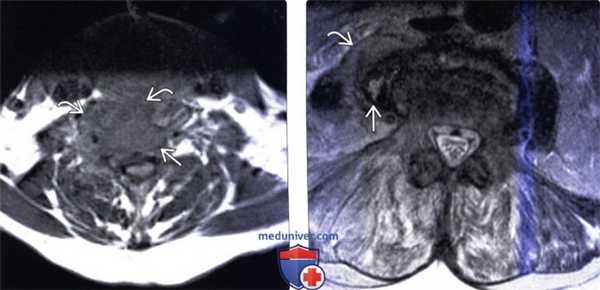

(Слева) Аксиальный срез, Т1-ВИ: аморфное низкоинтенсивное образование в области тела шейного позвонка и вентральной поверхности длинных мышц шеи. Паравертебральная флегмона стала следствием спондилодисцита.

(Справа) Аксиальный срез, Т2-ВИ: гетерогенное жидкостное образование в толще правой поясничной мышцы. Оно окружено толстой неправильной формы гипоинтенсивной стенкой, центральная часть отличается гиперинтенсивностью сигнала. Правая поясничная мышца с признаками диффузного усиления сигнала вследствие отека.